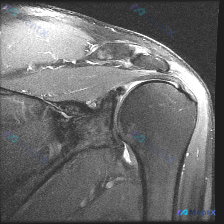

肩部MRI发现软组织积液,原来关键线索不在积液在这里

刚整理了一份肩部MRI的读片病例,核心问题是影像上可见软组织液体积聚,把我的分析思路分享出来和大家讨论。

这是一份肩部MRI冠状位T2加权图像,核心问题是问影像上可见的软组织液体相关分析,以下是完整的影像观察:

- 骨性结构:肱骨头、肩胛盂、肩峰轮廓清晰,无骨折、骨质破坏、关节面塌陷,肱骨头大结节骨皮质完整

- 冈上肌腱:肱骨大结节止点处可见片状异常高信号,局部肌腱连续性受影响,形态变薄

- 其他肌腱:肩胛下肌等其他肌腱在此截面未见显著异常信号

- 肩峰下区域:肩峰形态平直,无钩状突起或明显骨赘;冈上肌腱上方肩峰下-三角肌下滑囊区域局部信号增高

- 盂肱关节与盂唇:关节间隙无明显增宽或狭窄,盂唇未见明确撕裂征象